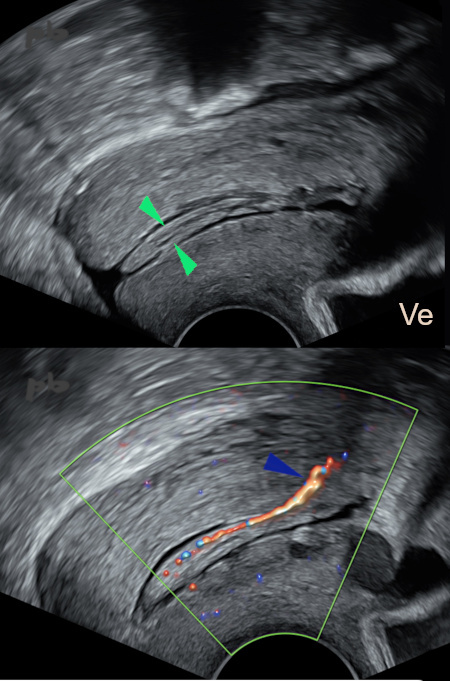

7 – Polype endocervical

Echographie endovaginale – coupes sagittales centrées sur le col.

Visualisation d’une image allongée dans le canal cervical (►).

Le doppler couleur montre le pédicule vasculaire (►), se rattachant à la face postérieure de la région cervico-isthmique.

Ve = vessie